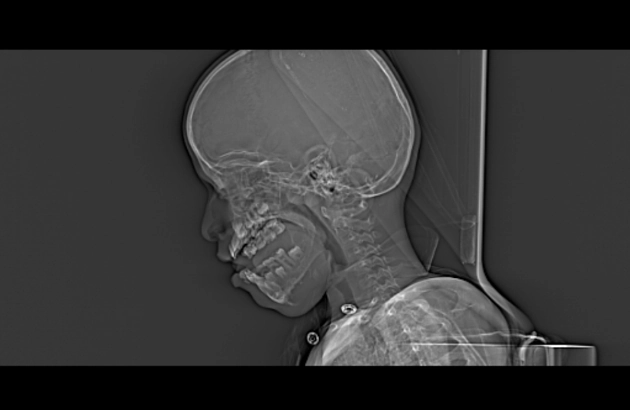

Loạn sản xơ xương (Fibrous dysplasia - FD)

Loạn sản xơ tạo xương (Osteofibrous dysplasia)

U xơ tạo xương (Ossifying fibroma)

U xơ không cốt hóa (Non-ossifying fibroma - NOF)